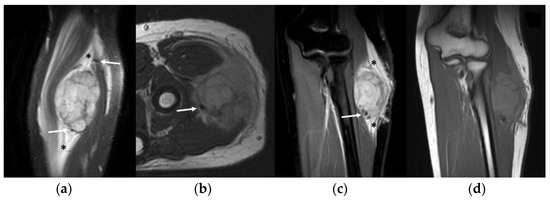

3.4. MRI Features